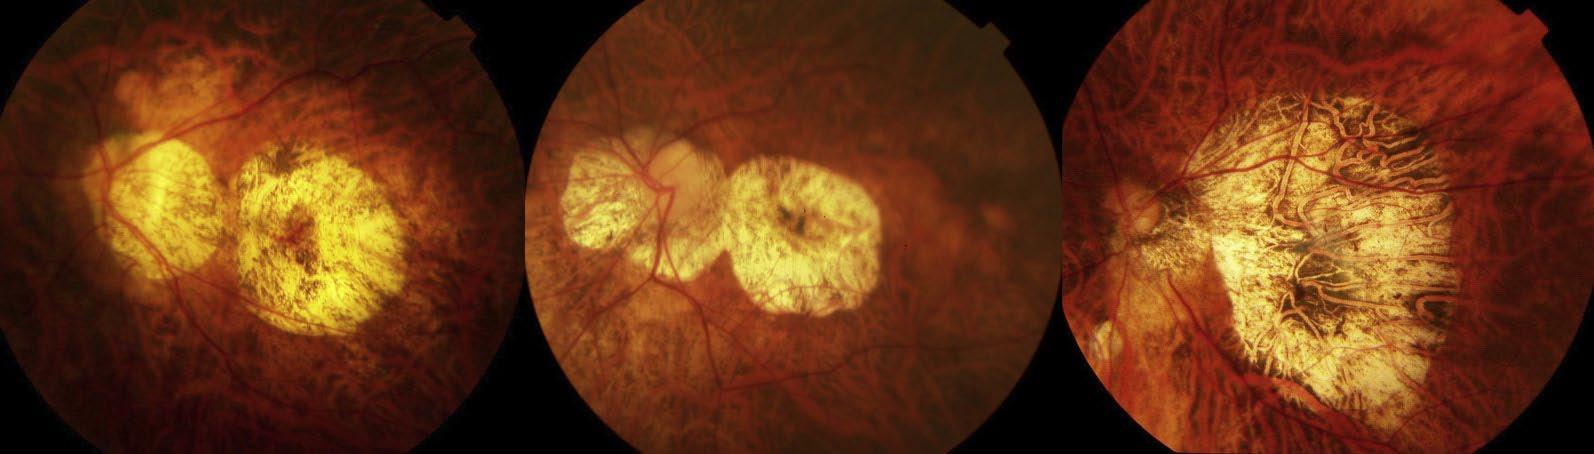

Si presenta con lesioni giallo-grigiastre, ben definite, di dimensioni variabili, localizzate nell’area maculare o attorno alla papilla ottica. L’atrofia corioretinica localizzata è caratterizzata dalla perdita completa della coriocapillare e può causare la perdita degli strati retinici esterni e dell’EPR. Sono identificabili tre tipi di atrofia corioretinica localizzata: uno che deriva dalle lacquer cracks, uno che si forma all’interno di un’area di grave atrofia corioretinica diffusa e uno che si sviluppa lunga il bordo di uno stafiloma. Nella figura 4 possiamo vedere delle fotografie standard di atrofia corioretinica localizzata. In alto a sinistra e a destra aree di atrofia corioretinica localizzata di dimensioni inferiori a 1 all’area del disco ottico (DA). In basso a sinistra atrofia corioretinica localizzata di oltre 9 DA con atrofia maculare. In basso a destra atrofia corioretinica localizzata di oltre 9 DA.

fig. 4 Figura 4

della coriocapillare e può causare la perdita degli strati retinici esterni e dell’EPR. Sono identificabili tre tipi di atrofia corioretinica localizzata: uno che deriva dalle lacquer cracks, uno che si forma all’interno di un’area di grave atrofia corioretinica diffusa e uno che si sviluppa lunga il bordo di uno stafiloma. Nella figura 4 possiamo vedere delle fotografie standard di atrofia corioretinica localizzata. In alto a sinistra e a destra aree di atrofia corioretinica localizzata di dimensioni inferiori a 1 area del disco ottico (DA). In basso a sinistra atrofia corioretinica localizzata di oltre 9 DA con atrofia maculare. In basso a destra atrofia corioretinica localizzata di oltre 9 DA.